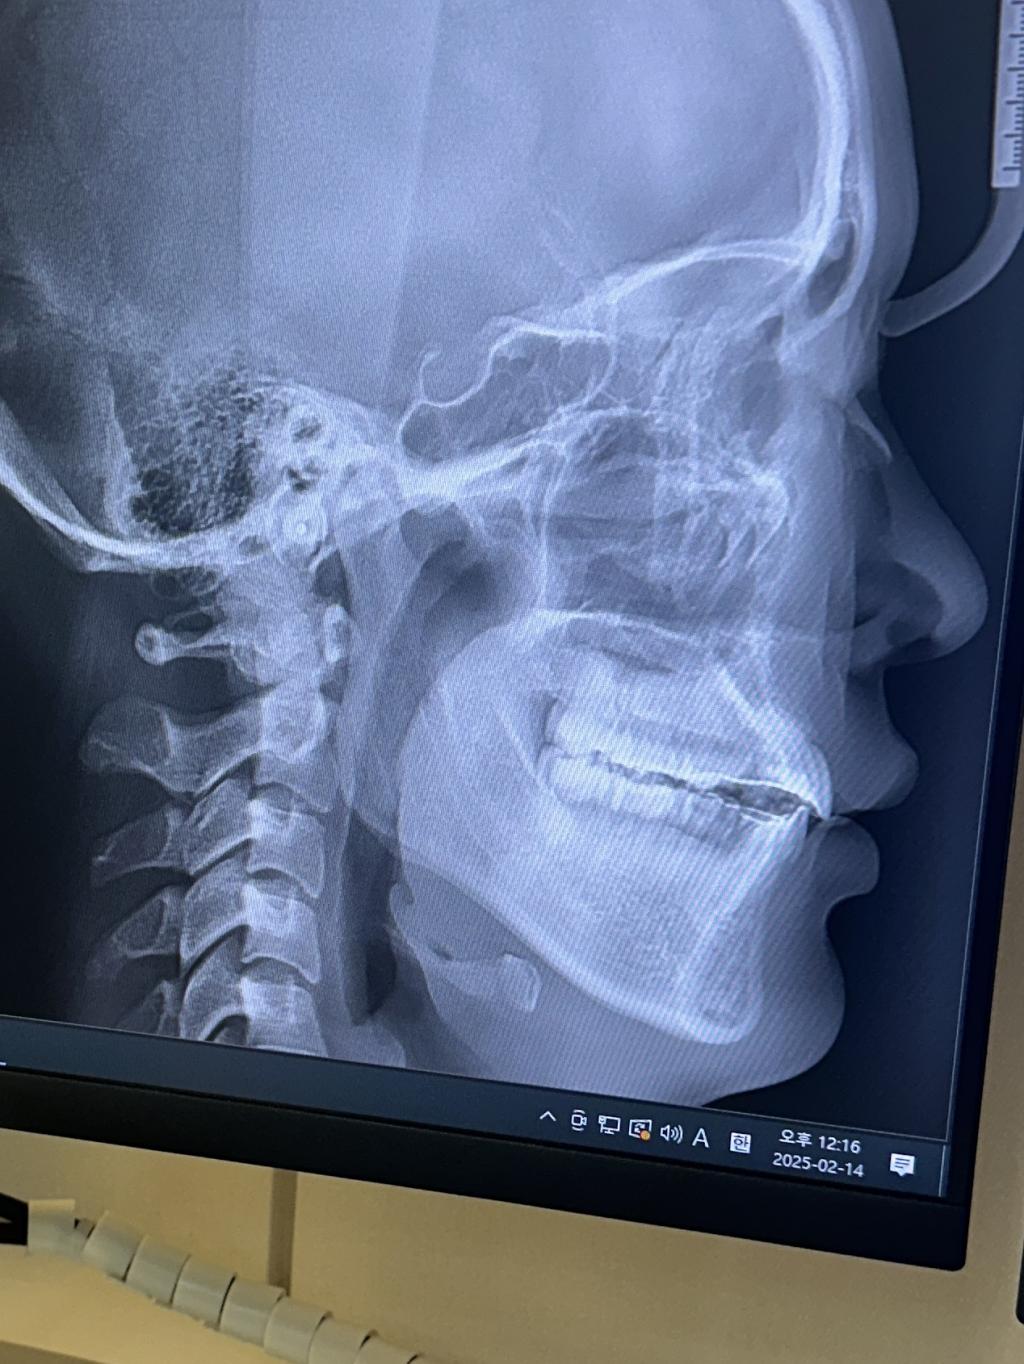

이상적인 상악 앞니의 각도는 95도라고 하는데

저의 상악 앞니의 각도가 115도가 넘어보이시죠..?

완료된 사진입니다,, 앞니가 덜 넣은게 맞는거죠.. 더 넣고싶어요..

앗 발치는 사랑니3개에 작은어금니들4개 했습니다!